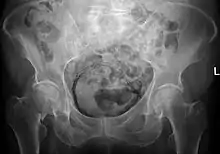

![]() | |

Regulation of urine production by ADH and aldosterone | |